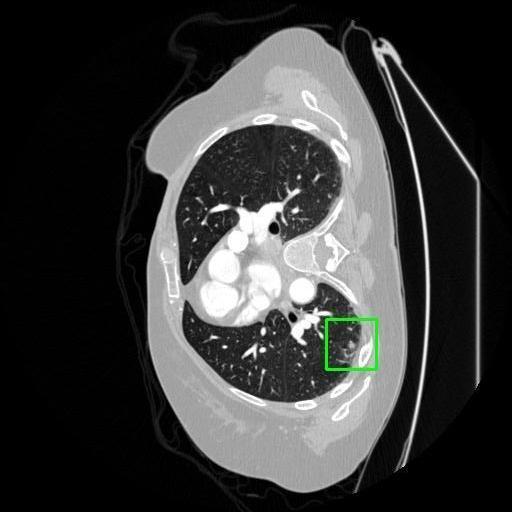

We developed an AI-based system using deep learning models for analyzing lung CT scans to detect and classify pulmonary nodules. We chose the YOLOv11 architecture for its enhanced object detection capability and adapted it specifically for medical imaging, incorporating pixel-level precision and severity classification.

Classification into three severity levels with colored bounding boxes.

Maintaining performance on small, complex features like micro-nodules tested the limits of traditional object detectors.

Designed a severity classification system that categorizes nodules into null, moderate, and severe using colored bounding boxes, assisting in rapid clinical decision-making.